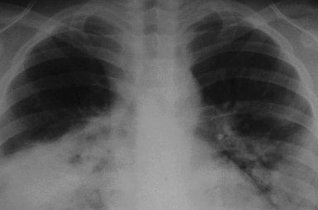

白肺的意思是指胸片、CT上发现正常肺组织透X线是黑色,只有心脏和大血管是白色,但是由于各种疾病、各种致病因素,导致两肺野呈大片的密度增高,出现白色的阴影,就...47600人收听

白肺一般是指重症肺炎在X光检查下的表现,肺部呈现一大片的白色状态而闻名。形成白肺一般都预示着肺部被炎症所广泛浸润,引起白肺的病因往往非常复杂,并且来势凶...28117人收听

白肺是指患者在X光胸片检查或者肺部CT检查中,肺部间质组织呈现大片状白色状病变的表现。白肺的症状表现多发生于重症肺炎,因为肺部间质组织持续性受到病毒、细...60057人收听

白肺(White lung)是一种临床综合症,其特征是重度肺炎患者的肺部积累了大量渗出物,影响多个肺叶,使肺部影像学检查呈现出大范围的白色区域。病因多为新型冠状病毒感染、细菌性肺炎、中东呼吸...

[最佳答案] 白肺是放射学名词,所谓白肺是指胸片或者CT上弥漫的高密度影,使得片子看不到肺纹理。导致白肺发生的原因很多,常见的大叶性肺炎、肺水肿,或者是病毒性肺炎比如SARS,以及流感、病毒引起的肺炎都会导致白肺。 至于能不能治愈要根据疾病的不同来决定, 白肺是放射学名词,所谓白肺是指胸片或者CT上弥漫的高密度影,使得片子看不到肺...